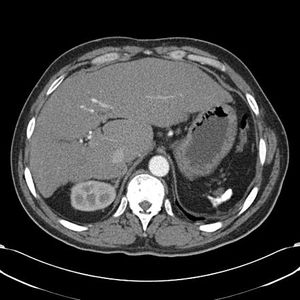

- absent spleen on CT